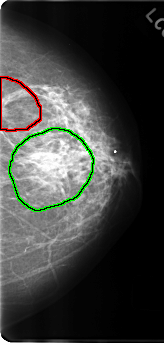

C_0191_1.LEFT_CC

FILE: C_0191_1.LEFT_CC.OVERLAY

TOTAL_ABNORMALITIES 2

ABNORMALITY 1

LESION_TYPE MASS SHAPE IRREGULAR MARGINS ILL_DEFINED

ASSESSMENT 5

SUBTLETY 5

PATHOLOGY MALIGNANT

TOTAL_OUTLINES 1

BOUNDARY

ABNORMALITY 2

ASSESSMENT 4

SUBTLETY 4